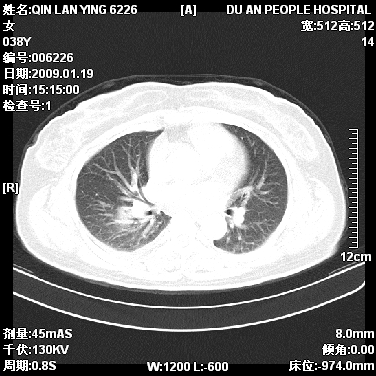

女,38岁,胸疼1个月。wbc:1万4

1)右肺中央型肺癌并右肺上叶阻塞性肺炎、节段性肺不张,纵隔淋巴结转移、右侧胸膜转移、肝脏转移。2)右侧胸腔少量积液。

1、右侧中央型肺癌并阻塞性肺不张,纵隔内、主动脉弓旁、右肺门淋巴结及肝脏转移可能性大,建议纤支镜进一步检查。

2、右侧胸腔积液。

本病例有几个容易诊断的地方:1、右肺上叶前段支气管闭塞,肺不张。2、淋巴结明显肿大。3、肝脏多个类圆形低密度影呈“牛眼征”改变,高度提示转移。

从影像学角度分析      右肺上叶中央型肺癌,并阻塞性不张、肺炎,纵隔淋巴结、膈顶淋巴结转移。

肝内两个大小不等低密度结节,内可见更低密度影,首先考虑肝内转移瘤,但联想到患者wbc1万4,建议楼主还是做个增强比较明确,除外肝脓肿的可能。